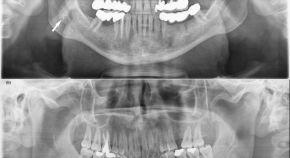

Digital radiography in dentistry articles from across Nature Portfolio